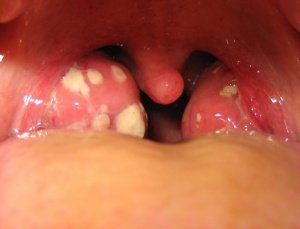

гнойная ангина